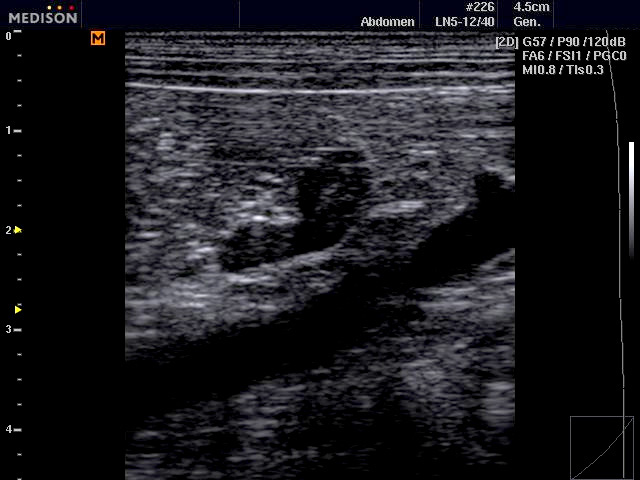

A készülék kapható állatorvosi vizsgálatokhoz szükséges vizsgálófejekkel kisállatok és nagyállatok vizsgálatához az ehhez szükséges optimális frekvenciatartományokkal.

Egyes készülékek rendelkeznek kisállat és nagyállat biometriás táblázatokkal és testábrákkal is a dokumentáláshoz.